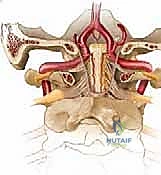

The vertebral artery is a major vessel that ascends through the foramina transversaria from C6 up to C1. After traversing the foramen transversarium at C1, it makes a sharp, critical turn. It courses medially and posteriorly, lying within the groove on the posterior arch of C1. It then passes through the posterior atlanto-occipital membrane before ascending through the foramen magnum, merging with its contralateral counterpart to form the basilar artery.

FIG 1 • E. The vertebral artery ascends through the foramina transversaria from C6 to C3. It takes a turn laterally through C2 underneath the pars interarticularis. Once it traverses the transverse foramen at C1, it turns medially and lies on the superior surface of the C1 ring. F. After passing medially on the superior surface of the C1 ring, the vertebral artery passes through the foramen magnum and merges with its counterpart to form the basilar artery.